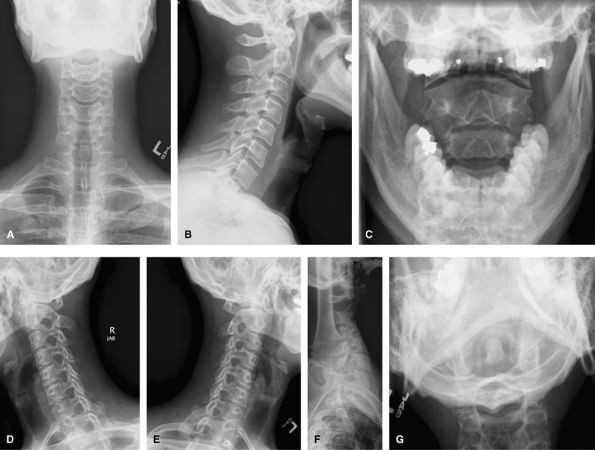

Cervical Spine

Complete

Include a swimmer’s view if C7–T1 junction is not well

visualized on the lateral view, and a Fuch’s view if the odontoid is

suboptimal. Such a full series is rarely used and would be replaced by

CT for acute trauma and CT or MRI for chronic pain/radiculopathy.

Oblique views such as these would be difficult in the trauma setting and

would be done as trauma obliques with the patient supine and the beam

angled obliquely. They can be useful to show the posterior elements,

particularly at the cervicothoracic junction where it may otherwise be

difficult.

Figure 50 (A) AP. (B) Lateral. (C) AP odontoid (open mouth). (D) Right anterior oblique (wrongly labeled). (E) Left anterior oblique. (F) Swimmer’s view to visualize C7–T1. (G) Fuch’s view.

Limited

A more reasonable series for acute trauma. Follow-up or chronic pain would usually emphasize the area of interest.

Figure 51 (A) AP. (B) Lateral. (C) AP odontoid (open mouth). (D) Swimmer’s view